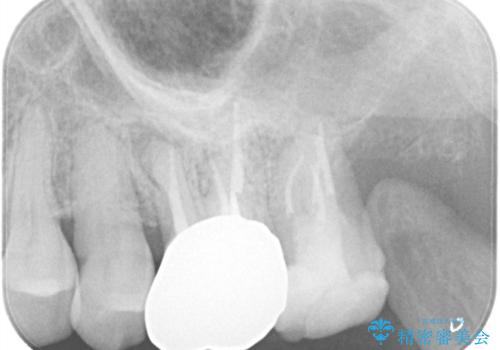

【根管治療】ズーンと痛い歯の治療。

- 奥歯付近がジーンと痛いことを主訴に来院されました。

左上7番の歯は、歯髄検査にて反応を示し、歯周ポケットはありませんでした。

親知らず抜歯を行い、痛みの変化や歯根吸収の有無を確認したのち、抜髄処置を行っています。

症状改善し、遠心の骨の回復も認めます。

バイオセラミックシーラーを使用して根管充填を行っています。